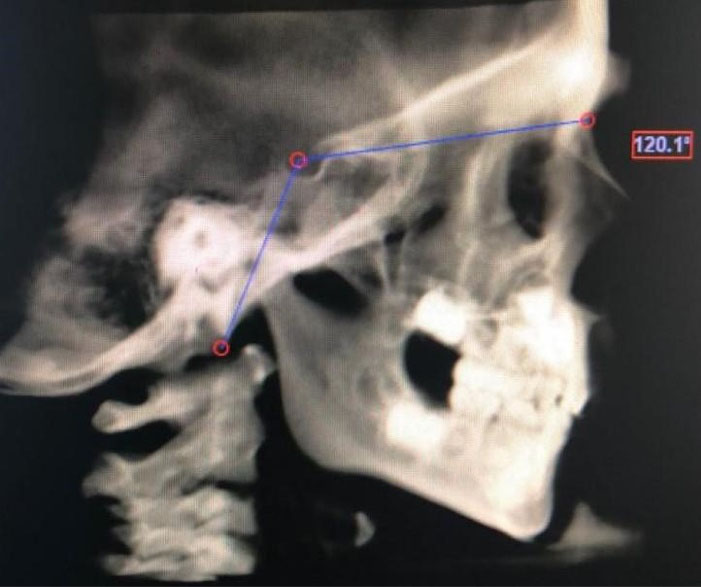

Figure 1.

Measurement of BaSN angle

| BaSN | The angle created between basion, sella, and nasion points |